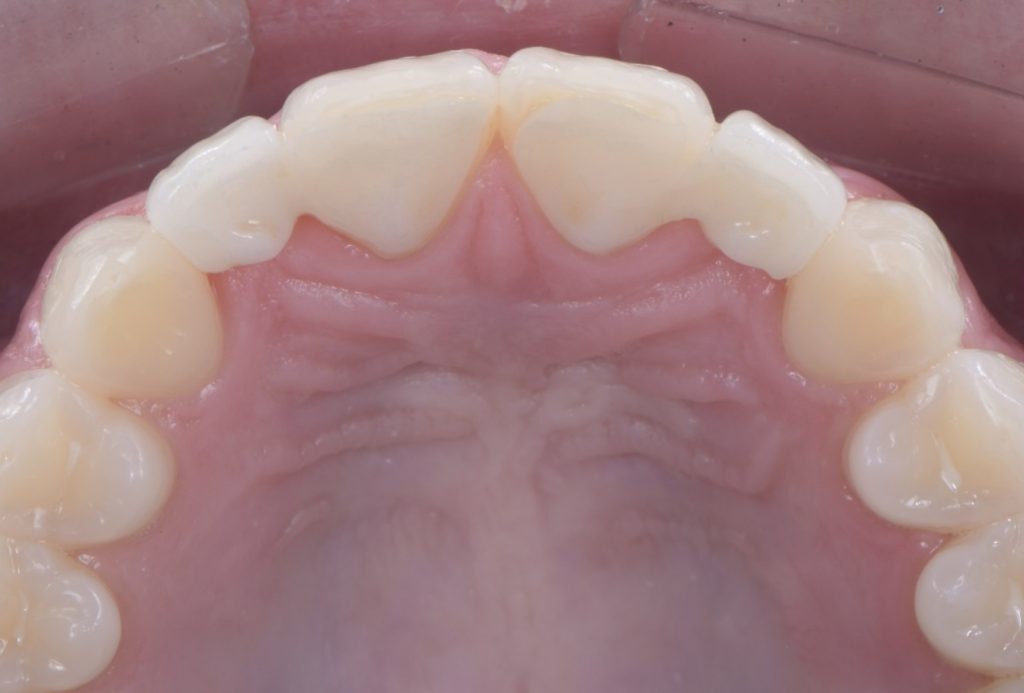

In this case, a 16-year-old female (Figs. 13-23) presented with congenitally missing lateral incisors with significantly undersized canines that were out of occlusion. Both these specific features meant that from a functional and esthetic standpoint (tooth position and size), the canines required additional contour to attain a favorable occlusal contact and a more dominant contour, characteristic of a maxillary canine.

So, I needed to make sure that there was enough space for the restorative material. A purely additive wax-up was required to attain a mockup, verifying that the proposed contours were esthetically pleasing. This can be obtained either by an analogic approach (Fig. 15) or a digital approach (Fig. 16).

Incisally, there was no reduction required, the reduction was minimal, and from a cervical perspective, a 0.5 mm finish line was prepared (Fig. 17). This allowed our team to do a fundamentally additive design.

It is important here to emphasize that even if the age and preference of the patient allowed us to plan for an implant-supported restoration to replace the lateral incisors, the need to enhance the contours of the canines would still be required to provide a functional and esthetically pleasing result.

The undersized canines were out of function, removing all protective coverage for the lateral incisors. This provided a unique opportunity and indication for the most conservative scenario of a cantilevered RBFDP.

When considering a zirconia crown, we needed to ensure there was sufficient room for the wall thickness to be a minimum of 0.3 mm (ideally between 1.0 mm and 1.5 mm), an incisal reduction of 2.0 mm, and a visible and continuous circumferential chamfer with a reduction of at least 0.5 mm at the gingival margin. The patient’s preliminary condition allowed us to accomplish these space requirements with hardly any tooth reduction (Fig. 17).